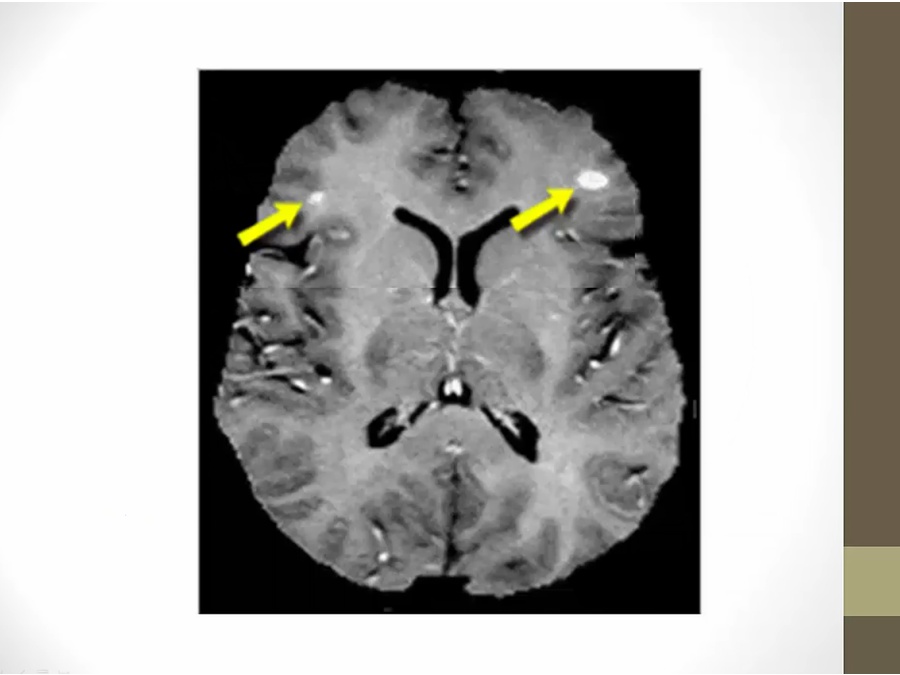

40 Demyelinating Diseases

MS